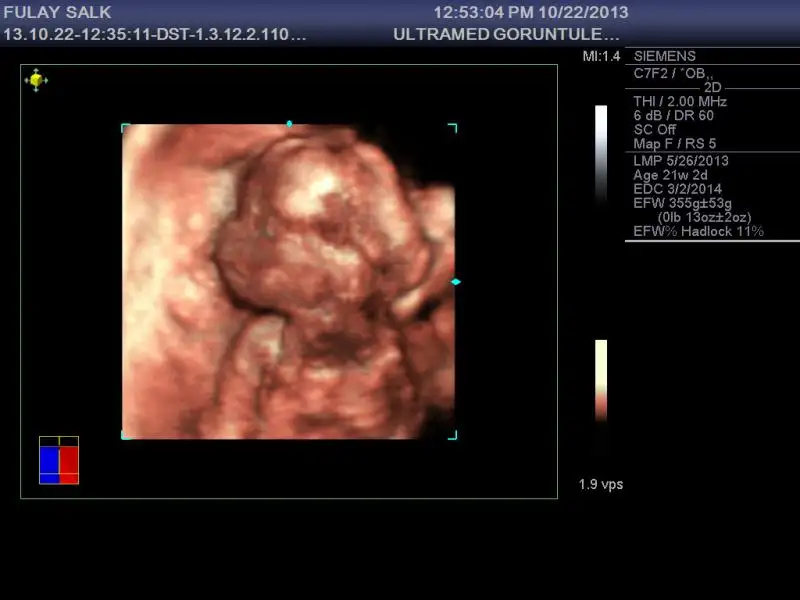

bu fotografa takmış herhalde doktor